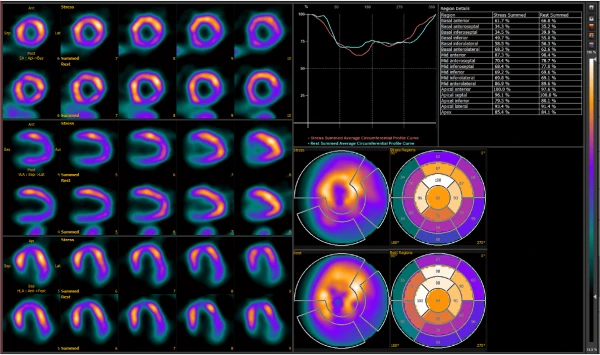

AnyScan TRIO® SPECT/CT tasvirlash tizimi ideal SPECT piksellar sonini va yuqori tasvir sifatini murosasiz taqdim etadi. Noyob uch boshli detektor dizayni suratga olish vaqtini qisqartirish orqali batafsil tasvirlarni olish imkonini beradi. Tizim qo'shimcha KT quyi tizimi bilan yadroviy tibbiyot uchun ideal multimodal uskunaga aylanadi. Ko'p teshikli kollimatsiya qo'shilishi bilan AnyScan TRIO® tizimi molekulyar tasvirlashda yangi zamin yaratadi. Xususiyatlari va afzalliklari Optimallashtirilgan vaqt-sifat-doza Klinik yadroviy tibbiyot amaliyoti tasvir sifatini buzmasdan tasvirni olish vaqtini sezilarli darajada qisqartirishi mumkin bo'lgan yuqori samarali tasvirlash tizimlarini talab qiladi. Bu mutlaqo mantiqiy so'rov va bizning javobimiz AnyScan TRIO® SPECT/CT multimodal tasvirlash tizimidir. Qisqartirilgan tasvirni olish vaqti: O'rtacha tasvirni olish vaqtini chorakgacha qisqartirish mumkin. Butun tananing SPECT/CT suyak skanerlashi 20 daqiqadan kamroq vaqt ichida bajarilishi mumkin. Rasmni olish vaqtini qisqartirish bemorning qulayligini yaxshilashga yordam beradi va harakat artefaktlari ehtimolini kamaytiradi. Tasvirning maksimal sifati: diagnostika aniqligi va ishonchliligini oshiradi. An'anaviy qo'sh detektorli boshga o'rnatilgan SPECT tizimlariga nisbatan sezilarli darajada yuqori tizim ruxsati va kontrast-shovqin nisbati ikki baravar yuqori. Kamaytirilgan ma'mur yuki: bemorning nurlanish dozasini kamaytiradi va administrator xavfini kamaytiradi. Amaldagi izlagichlarning kamroq soni radioaktiv izlagichlarning o'rtacha narxini dinamik ravishda kamaytirish imkonini beradi.